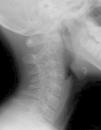

Se presenta una paciente de 11 años de edad que acudió al Servicio de Rehabilitación enviada por su pediatra por tortícolis resistente al tratamiento. En la exploración física se apreciaba una rotación de la cabeza hacia el lado derecho y una discreta flexión hacia el lado opuesto, con bloqueo de las rotaciones y las inclinaciones laterales, y con cierta flexo-extensión conservada. No existía compromiso neurológico. La familia recordaba un traumatismo leve 2 meses antes, con dolor de espalda varios días después, pero sin clara relación con el episodio actual. En la radiografía lateral de la columna cervical se apreciaba la masa lateral del atlas situada por delante de la apófisis odontoides (fig. 1). Posteriormente, se practicó una tomografía computarizada (TC) en la que se puso de manifiesto una rotación en el plano axial de C1 sobre C2, con luxación articular debida a la incongruencia de las carillas articulares de ambas vértebras (figs. 2 y 3), siendo el espacio atlo-odontoideo normal. La subluxación rotatoria de C1-C2 es una de las posibles etiologías de la tortícolis persistente, y aunque su frecuencia general es baja, es más habitual en niños1,2. El mecanismo lesional puede ser traumático o atraumático, siendo la mayoría de origen espontáneo3,4. Es muy frecuente que estos casos tarden en ser diagnosticados, por lo que ante una tortícolis resistente al tratamiento se debe sospechar, sobre todo si es precedido por un traumatismo leve1. La postura del paciente dificulta la exploración radiográfica, por lo que en estos casos está indicada la realización de una TC.